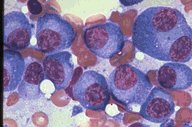

Multiple myeloma, high-oil mag, BMA

This high-oil magnification view is of a bone

marrow aspirate in a patient with multiple

myeloma. All cells in this field are neoplastic

myeloma cells. The nuclei are pleomorphic and

eccentric and the cytoplasm is a grey-blue.

One cell is binucleate.